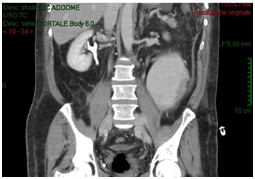

A 54-years old Caucasian man affected by sub renal aortic aneurysm, undertake vascular surgery of aortotomy and bilateral aortoiliac Dacron prosthesis implantation. Patient had a good health status; he had hypertension (with good control of blood pressure), diabetes mellitus type 2. He had no operations. In the past. In 5 post-operative days, due to post-operative anaemia, fever and slight increased creatinine (around 1.3 mg/dl), the patient received an ultrasound scan that showed intra-retroperitoneal fluid without any sign of hydronephrosis. In the suspect of haemorrhage, vascular surgeons performed an abdomen CT-scan with contrast that reported organized hematoma along the right iliac branch associated to intraperitoneal serous-hematic fluid (Figure 1). CT-scan did not have delayed phases. In XII post-operative day, patient was transferred to intensive care ward because of fever until 39°C, dynamic ileus and uremic status. He received an abdomen contrast CT-scan that showed increasing of intra-retroperitoneal fluid with small bowel and right colon compression and increase of right iliac region serous-hematic fluid (Figure 2).

Figure 2: CT-scan shows increasing of intra-retroperitoneal fluid with small bowel and right colon compression and increase of right iliac region serous-hematic fluid.